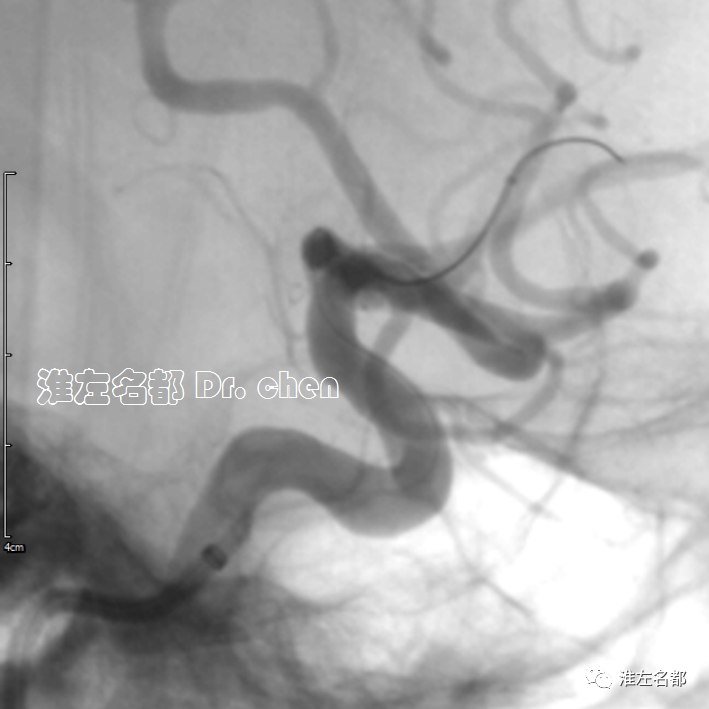

△采用同轴技术将6F长鞘(90cm,Cook)送至左侧颈总动脉,造影:左侧颈内动脉颅外段螺旋样延长迂曲,经.035”泥鳅导丝将中间导管(Navien 072, 105cm)头端送至岩骨段(黑箭)。

△经中间导管造影:左侧大脑前动脉A2段闭塞(橙箭)。